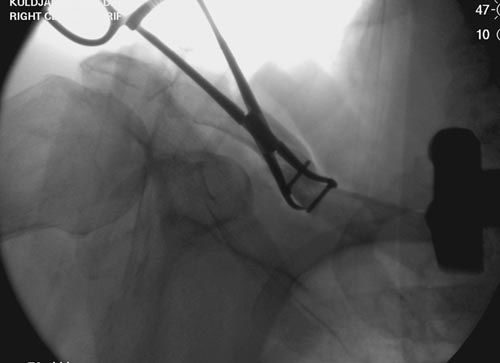

В заключение, только 25% изолированных переломов ключицы, леченных консервативным методом не срастаются, а из них 1/3 симптоматические. Болезненные ложные суставы надо оперировать, и здесь представлен случай свежего болезненного ложного сустава, оперированного через 4 месяца.

Освобожден средний фрагмент и боковая компрессия лагированием, фиксация пластиной..